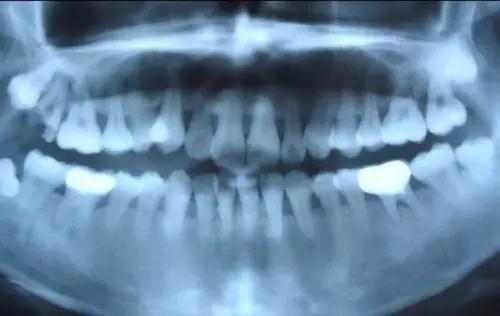

第三次全国口腔健康流行病学抽样调查结果显示,所调查的年龄组的牙结石检出率如下:

12岁年龄组:59%

35-44岁年龄组:97.3%

65-74岁年龄组:88.7%

国人口腔环境触目惊心!